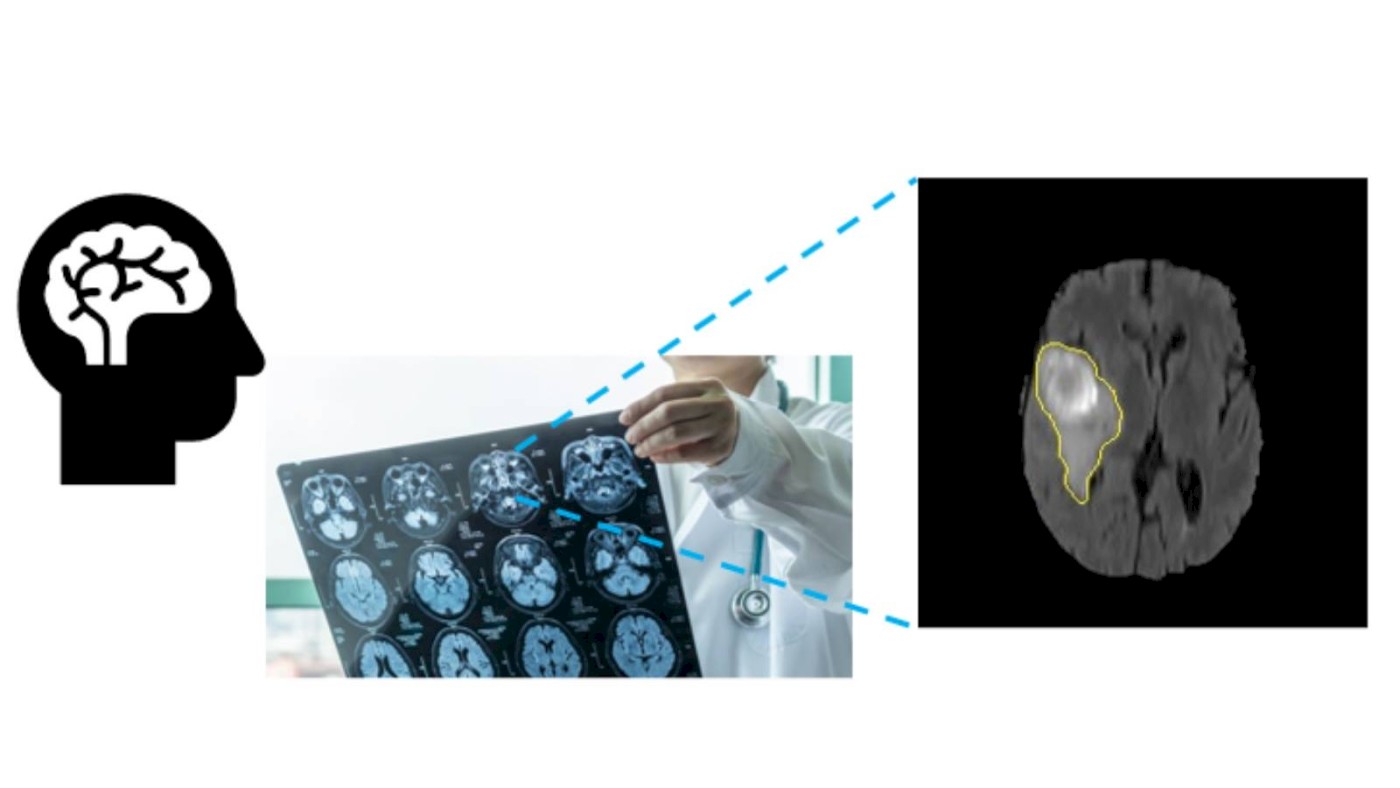

An AI-based digital solution for tumour characterisation has brought Ahmedabad University professors to the forefront of medical research. This development integrates advanced deep learning and radiomics to non-invasively diagnose and characterise brain tumours, addressing limitations in current diagnostic practices, which are heavily dependent on biopsies.

The challenge with current tumour diagnosis lies in understanding a tumour's microenvironment, which is crucial for accurately determining its grade and selecting the most effective treatment. At present, biopsies remain the gold standard for tumour diagnosis. However, they present several challenges: they are invasive, offer minimal information about the overall tumour, and can often be inconclusive or subjective during surgery. Such limitations may necessitate repeat surgeries, increasing patient burden and risk. This calls for a robust, non-invasive assessment procedure that can comprehensively examine tumour tissues using cutting-edge technology.

The research team includes Professor Jayendra M Bhalodiya (School of Engineering and Applied Science and the Bagchi School of Public Health) as the Project Investigator (PI), alongside Co-Investigators Professor Mehul Raval (School of Engineering and Applied Science) and Professor Kaumudi Joshipura (Dean and Professor at the Bagchi School of Public Health). The research team proposed an AI-based digital solution for tumour characterisation. The tool will be developed using convolutional neural networks (CNNs) and transformer-based architectures of deep learning alongside radiomics feature extraction methods. It will be tested using multi-sequence MRI data. Moreover, a feasibility study on glioma characterisation will be conducted to validate the tool using suitable histopathology and/or genomics data.

The team aims to develop a deep neural network-based tool that can process 3D volumes of multi-sequence MRI and provide segmented tumour areas for analysis using radiomics features. These features are quantitative measures that can be used to train a machine learning classifier to characterise tumours. Such AI tools can help determine tumour grade non-invasively and with greater accuracy. Furthermore, the derived radiomics features may help identify potential image biomarkers. Open-access data from the Cancer Genome Atlas (TCGA) repository will be used to develop the model and conduct experiments.

The development of this AI-based tool for brain tumour segmentation, characterisation, and diagnosis holds potential by offering a comprehensive, non-invasive, and accurate assessment method. It holds promise to revolutionise tumour diagnostics, potentially reducing the need for invasive biopsies and providing more precise information to guide patient treatment. This advancement could improve outcomes and enhance the quality of patient care.